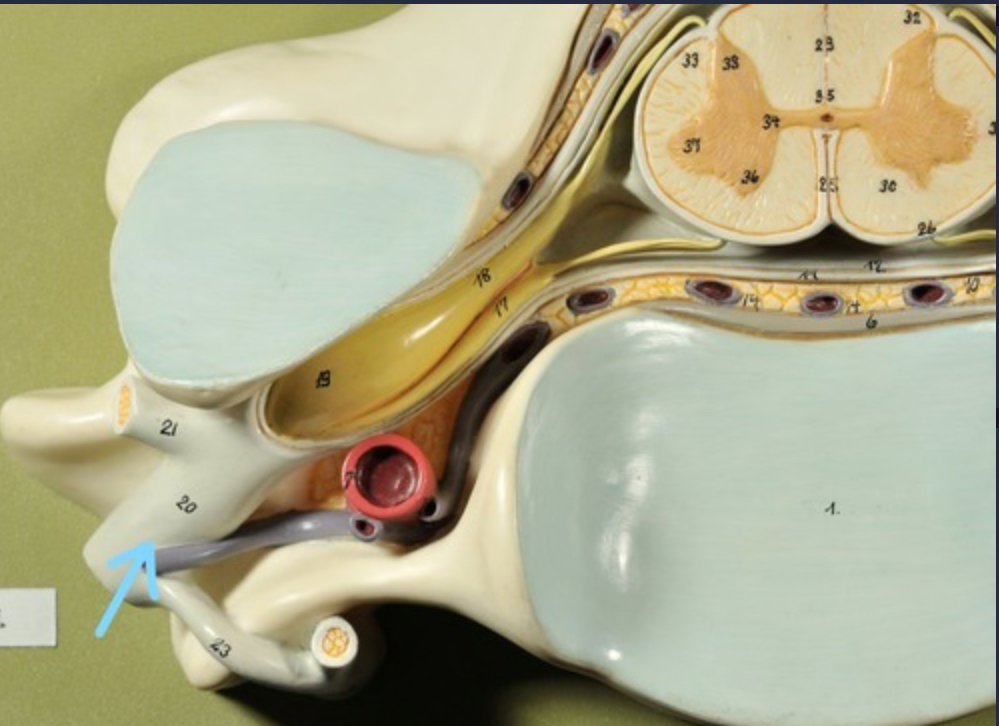

Spinal cord

Cauda equina

Dura mater (outermost layer)

White matter of spinal cord

Gray matter of spinal cord

Ventral horns (of gray matter)

Lateral horns

Dorsal horns

Anterior columns of white matter

Lateral columns of white matter

Posterior columns of white matter

central canal of spinal cord

Pia matter

Subarachnoid space

Arachnoid matter

Subdural space (brown line)

Dura matter

Epidural space

Dorsal root ganglion

Dorsal root

Ventral root

Spinal nerve